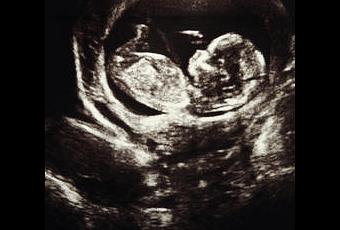

Dans les hôpitaux, les appareils les plus innovants sont souvent très chers. C’est d’après ce constat, que des chercheurs de Newcastle ont fabriqué un scanner à imagerie ultrason low cost. Des dispositifs dont le prix variaient entre 75000 à 300 000 euros pour les plus coûteux. Actuellement, le marché propose des dispositifs moins chers qui n'ont cependant pas la même qualité d’imagerie, ni la même précision. Ainsi, Jeff Neasham et Dave Graham, de l’université de Newcastle, ont développé un scanner médical à balayage ultrasonique de poche à l’attention des fœtus et des bébés. Ce scanner a été conçu pour les hôpitaux qui ne peuvent avoir ce type d’appareil car le prix est prohibitif. Il posséderait néanmoins les mêmes résultats que les modèles haut de gamme, pour un prix qui avoisinerait près de 7 500 euros.

En effet, les résultats obtenus ont démontré que les performances sont sensiblement identiques à celles d’un appareil haut de gamme; même grain au niveau de l’image, même qualité, et même précision. L’appareil de poche s'avère plus flexible et facile à utiliser grâce au port USB et ainsi il peut se connecter à n’importe quels ordinateurs. Cependant, plusieurs ajustements doivent encore être apportés. Avec de nouveaux composants, les chercheurs vont essayer de corriger le contraste et diminuer le « bruit » lié au signal d’ultrason en utilisant d’autres matériaux.